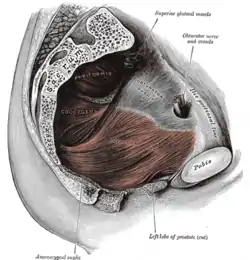

Median sagittal section of the sacrum. Left levator ani from within.

Left levator ani from within. The posterior divisions of the sacral nerves.